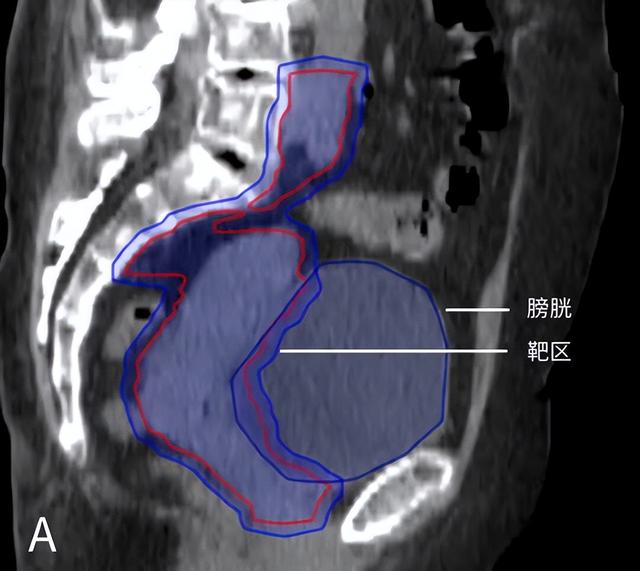

图为宫颈癌患者的矢状位图像。图A为计划CT,憋尿良好,肠道被推挤出盆腔;图B为治疗时的CBCT图像,憋尿较差,更多的肠道(红色箭头指示部分)进入照射区域。